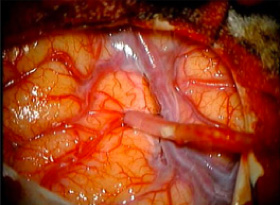

脳血行再建術(バイパス術)の術中所見

血管吻合中

血管吻合中

吻合完成

吻合完成

吻合完成

吻合完成